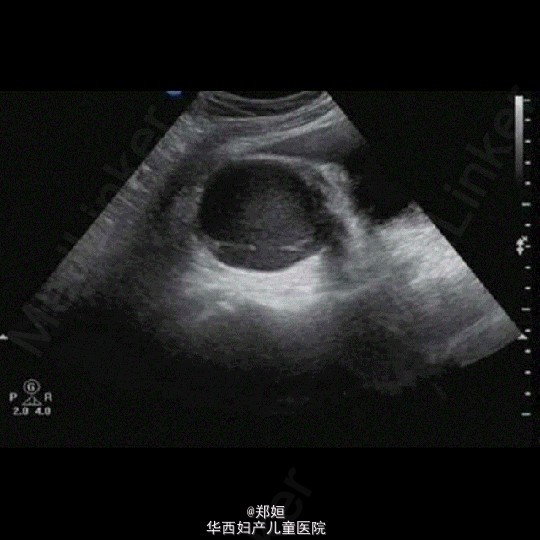

子宫腺肌症双侧卵巢囊肿超声表现

子宫腺肌症

卵巢囊肿

女,34岁,6年前体检发现右附件包块

子宫腺肌症双侧卵巢囊肿